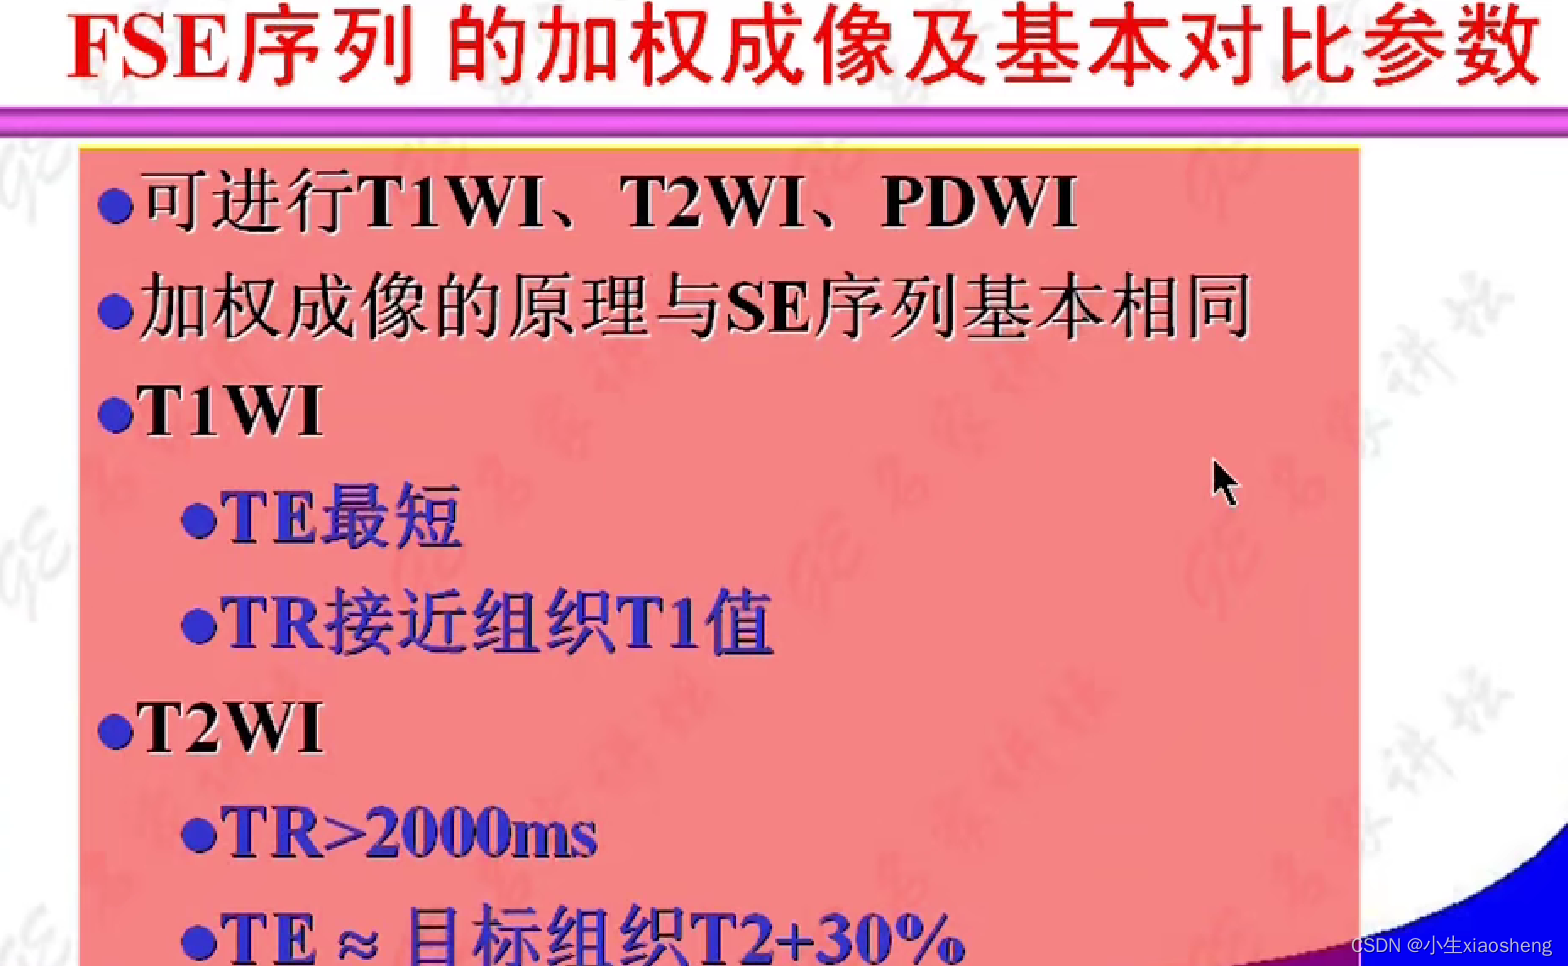

因为这里有很多的180度,所以一次能填充很多K空间线。两个90度之间的时间还是叫做TR,180度的个数叫做ETL,90度到中间个数的180度叫做有效TE,两个180度之间的叫做ES。

FSE序列图像尚脂肪组织信号增高